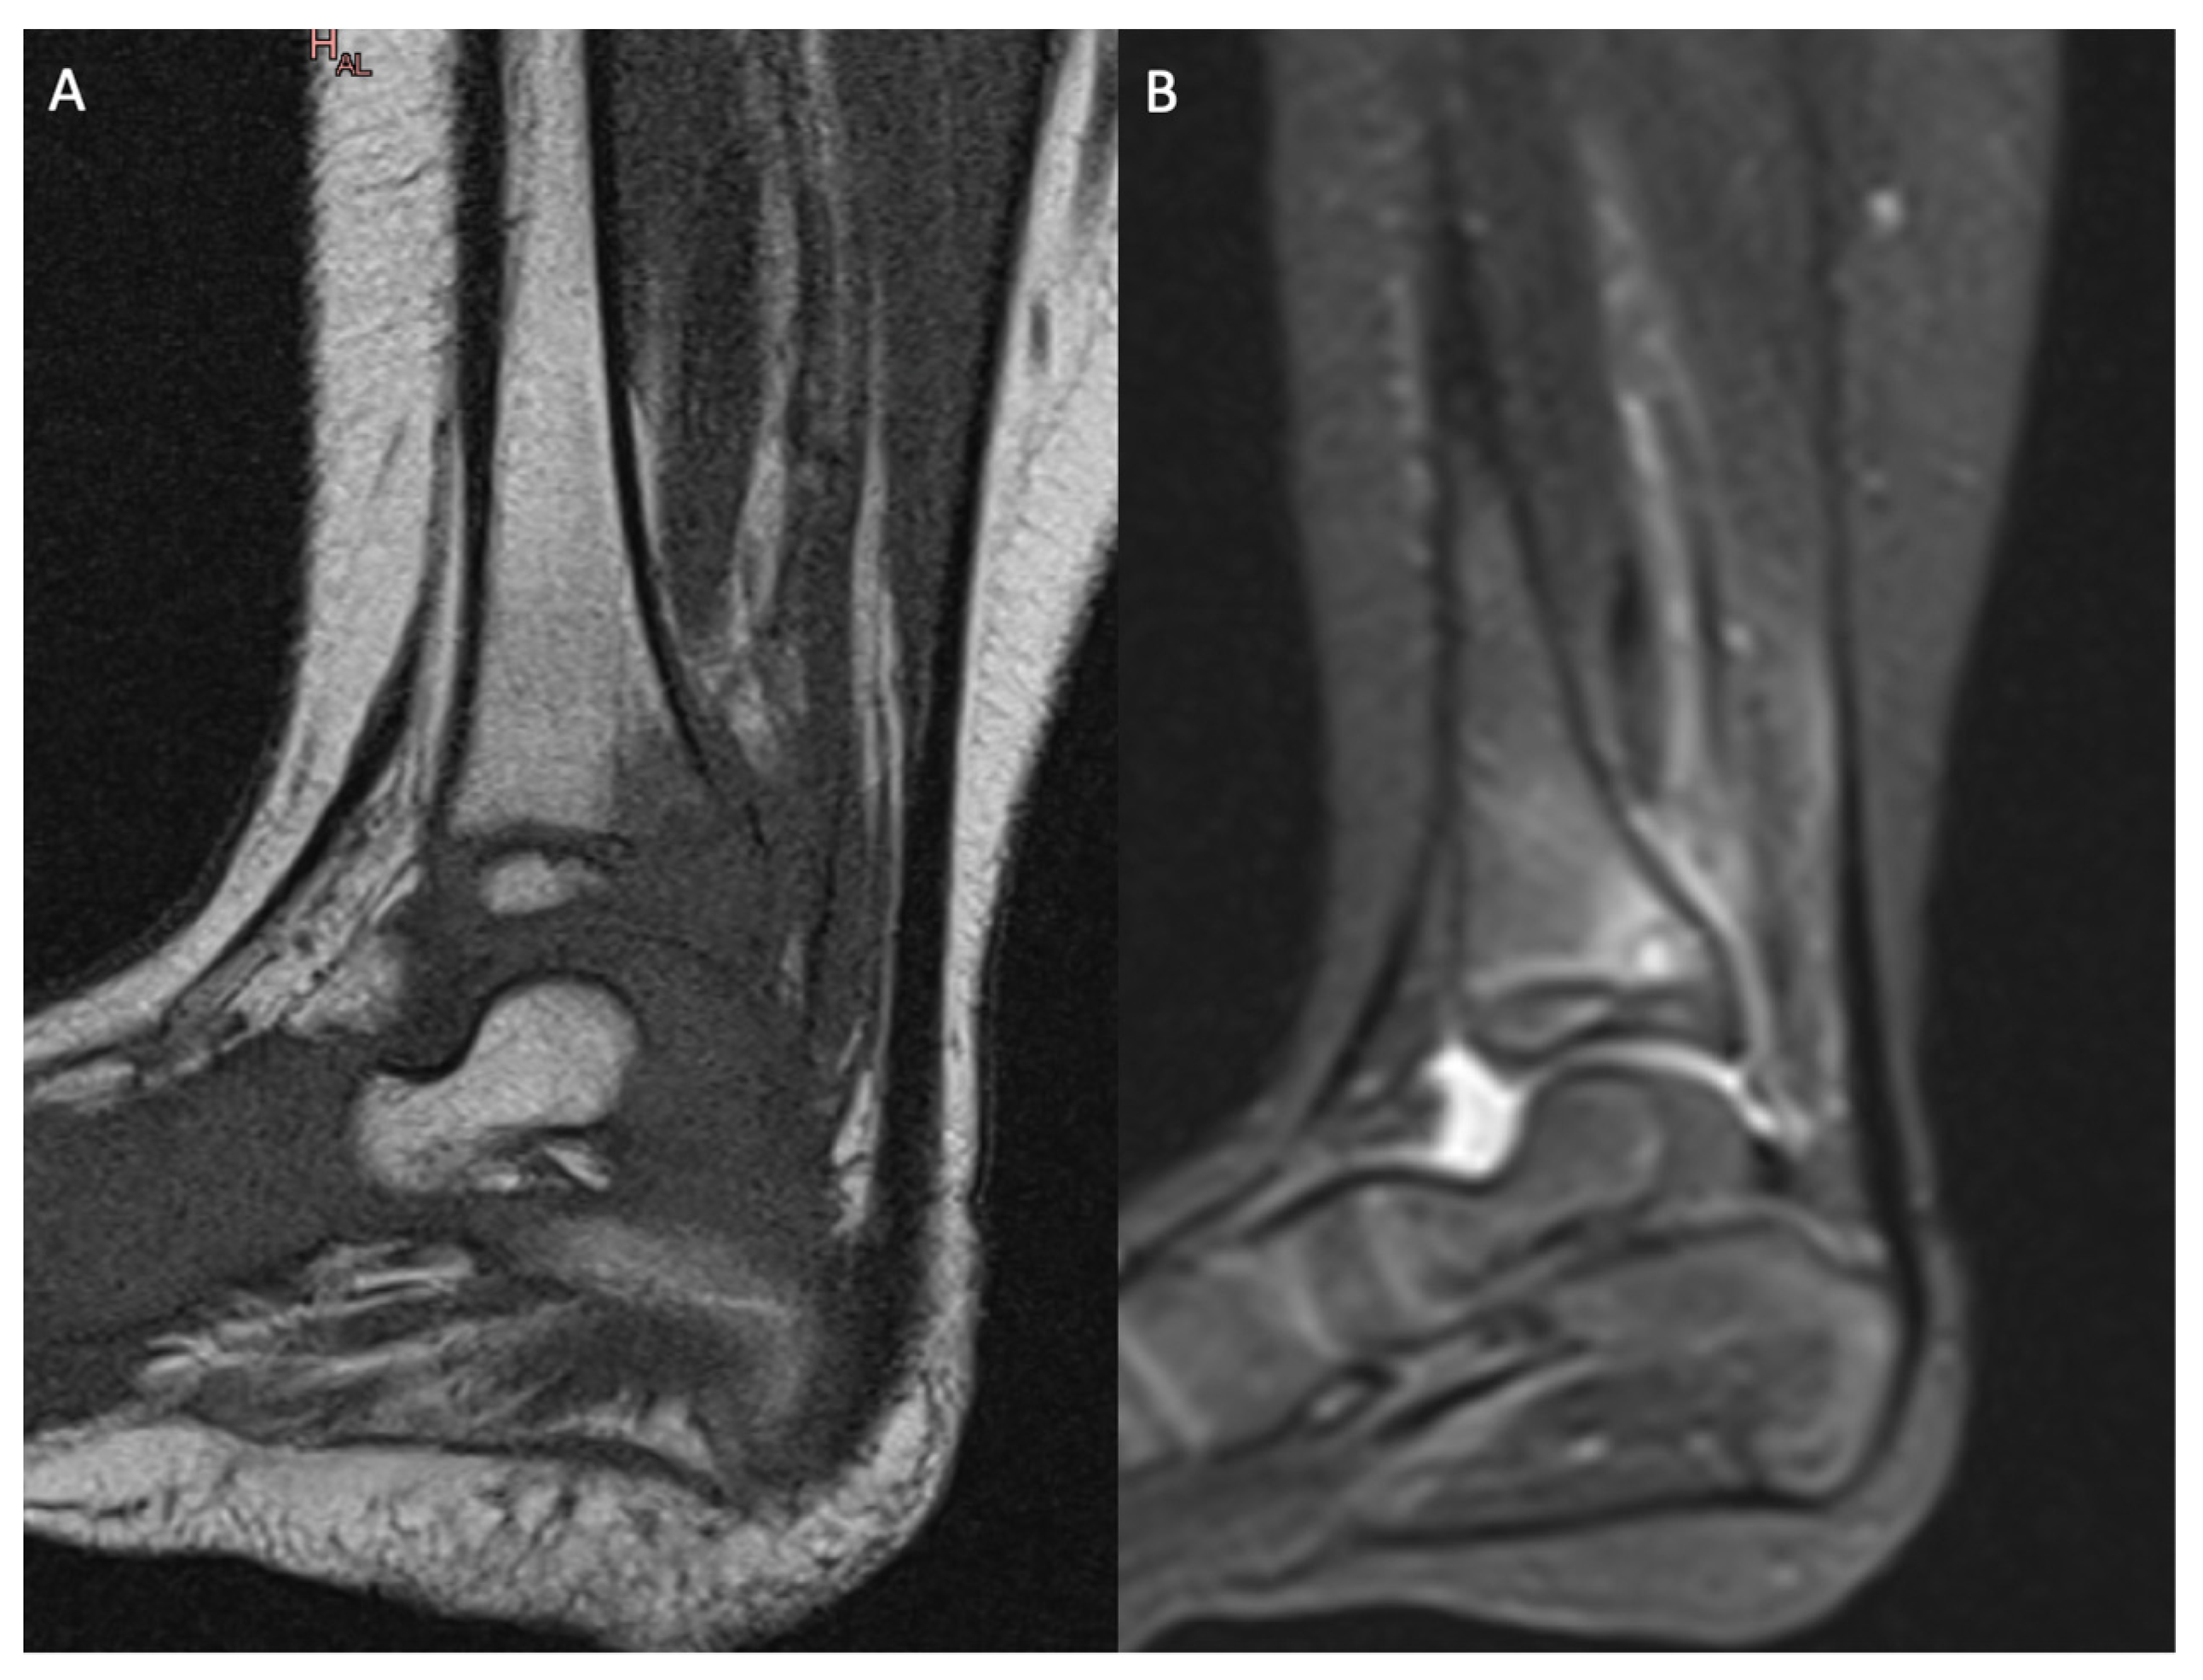

Thus, the presence of a vascular connection between the metaphysis and epiphysis could constitute a plausible explanation for transphyseal osteomyelitis in children younger than 18 months old or, at least, younger than 4 years old. However, in older children, the diffusion of the infection across the growing cartilage would undoubtedly have to involve either the unexpected persistence of transphyseal vessels or a different lesional process. As mentioned, several authors harbored doubts about growing cartilage’s impermeability to infection and, thus, its role as a barrier to spreading infection. Another pathophysiological hypothesis involves the bacteria lodged in the junction between the physis and the metaphysis—thus adjoining the physeal cartilage—causing an infectious erosion of the growing cartilage. A direct attack on the growing cartilage can be quick and brutal when pyogenic pathogens are involved (e.g., MSSA producing PV leucocidin; Figure 1). On the contrary, infectious erosion may be slower when due to less aggressive microorganisms (such as K. kingae; Figure 2). This last point suggests that the present study’s over-representation of subacute osteomyelitis in THO may validate this explanation.

Figure 2. MRI of the left ankle showing primary metaphyseal acute hematogenous osteomyelitis with transphyseal extension to the distal tibia due to Kingella kingae: (A) sagittal view of the left ankle with T1 sequence; (B) sagittal view of the left ankle with T2 STIR sequence.